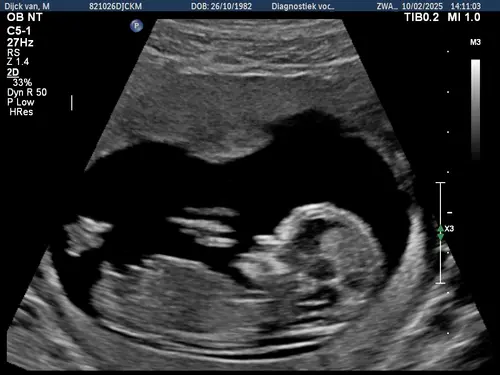

Vandaag de 13 weken echo gehad (13wk 2 dagen). Zien jullie op deze foto een Nub? Een jongetje of meisje?💙💖

Reactie op FantasierijkeHart501338

Vandaag de 13 weken echo gehad (13wk 2 dagen). Zien jullie op deze foto een ...

Foto 2